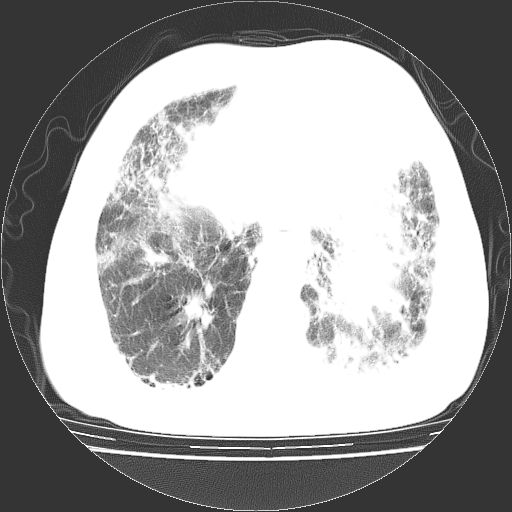

标题: CT25149:男,69岁,反复咳嗽、咳痰五年余,呼吸困难三天。 [打印本页]

男,69岁,反复咳嗽、咳痰五年余,呼吸困难三天。

慢支伴感染、肺气肿、肺心病!支持!另:间质纤维化!

两肺间质性炎症并感染,左上叶肉芽肿

考虑慢性间质性肺炎并肺间质纤维化。

慢支伴感染、肺气肿、肺心病。双肺间质性改变(间质纤维化)。